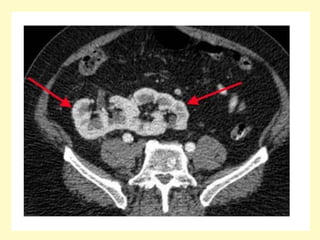

Horseshoe kidney with anteriorly oriented renal pelvis, axial contrast-

enhanced MDCT image (a) shows a horseshoe, the renal isthmus is

found anterior to the great retroperitoneal vessels, corresponding

volume rendering (b) better show the inferior renal isthmus, the

normal renal arteries, and the anterior location of the renal pelvises

I = isthmus, IMA (arrow)